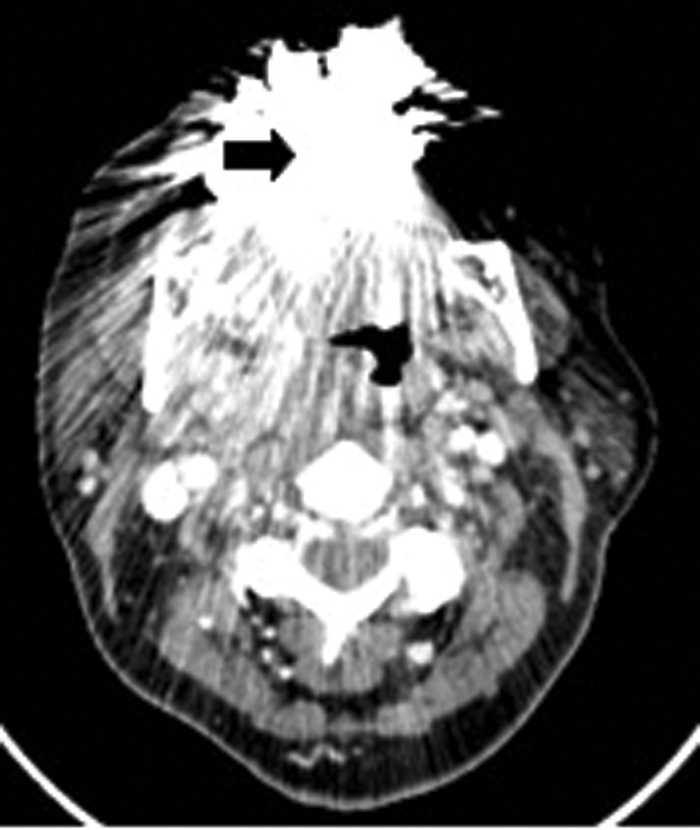

A 17-year-old male presented with a one week history of left otalgia and general malaise. Otoscopy was normal, but there was asymmetric left tonsillar enlargement. His inflammatory markers were raised suggesting sepsis.

CT (Figure 8) demonstrated a left peritonsillar abscess. In addition Figure 9 shows the patient to have bilateral calcified stylohyoid ligaments. Pharyngitis / tonsillitis are common causes of referred otalgia. Additionally calcification of the stylohyoid ligament greater than 28mm can compress the glossopharyngeal nerve causing dysphagia, tinnitus and otalgia, a collection of symptoms termed as Eagle’s Syndrome.

Figure 8: Contrast enhanced CT demonstrating a left peritonsillar abscess (white arrow).